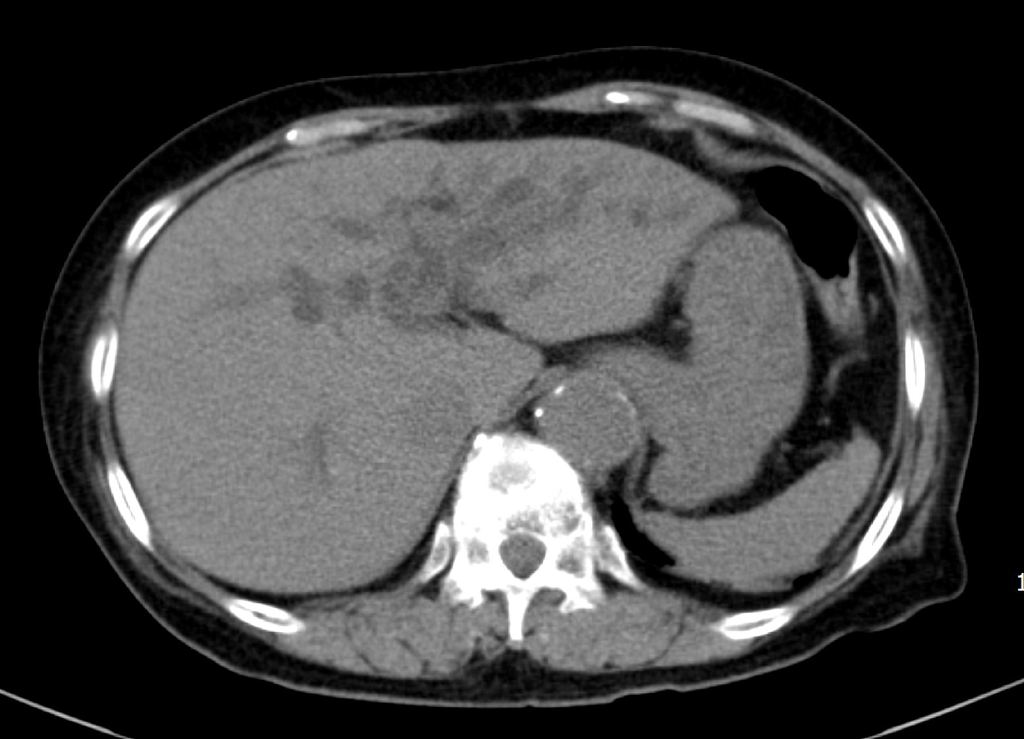

곧바로 촬영한 CT에서 여러개의 간내담관결석 및 전반적인 간내담관 및 간외담관 확장소견이 보입니다. 담관의 중심부 확장이 주변부 확장보다 더 심한 전형적인 proportional dilatation을 보입니다.총수담관(common bile duct)의 확장도 뚜렷하게 보이지만, 총수담관을 막고 있는 담관내 결석이나 국소병변 소견은 보이지 않습니다.

환자는 임상적으로나 임상검사 상 황달을 보이지 않았으며, CT 영상에서 간내담관결석 외에 담관의 확장을 일으킬 수 있는 병변은 확인되지 않았지만, 담관의 proportional dilatation은 장기간 총수담관을 막고 담즙의 배출을 방해하는 병변의 가능성을 암시합니다. 따라서 담관의 추가적인 확인을 위해 다음날 오전 초음파영상을 시행했습니다.